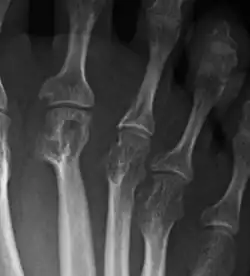

La artritis o inflamación de las articulaciones es la manifestación fundamental de la artritis reumatoide. Las articulaciones afectadas están hinchadas, calientes, dolorosas y rígidas, en especial al levantarse por la mañana o tras el reposo prolongado. Al principio pueden estar afectadas solo una o varias articulaciones, pero progresivamente se van sumando más articulaciones inflamadas —poliartritis—, siendo las que con más frecuencia se afectan las pequeñas articulaciones de las manos y los pies, aunque también es frecuente la afectación de otras articulaciones más grandes como los codos, los hombros, las rodillas o los tobillos.[49] La rigidez matinal es, con frecuencia, un dato destacado de la enfermedad y suele durar más de una hora. Estos datos ayudan a distinguir a la artritis reumatoide de otros problemas no inflamatorios de las articulaciones, como la artrosis u otros tipos de artritis. Las articulaciones se afectan habitualmente de un modo simétrico —afectando articulaciones semejantes en ambos lados del cuerpo—.[50] A medida que la enfermedad progresa, la inflamación articular causa erosiones y destrucción de las superficies articulares y daños tendinosos. Los dedos de las manos pueden sufrir diversas deformidades dependiendo de qué articulaciones y estructuras son las más lesionadas. Son deformidades típicas de la artritis reumatoide evolucionada los dedos en cuello de cisne, la deformidad en ráfaga cubital, la deformidad en boutonniere y el pulgar en Z.[49] La inflamación articular mantenida puede originar daños estructurales en las articulaciones, causando deformidad y pérdida funcional de la articulación afectada.[51][52]

La radiografía convencional es la técnica de imagen estándar de la artritis reumatoide. Los primeros signos radiológicos son la osteoporosis yuxtaarticular y el aumento de partes blandas. Estos cambios se siguen de la disminución del espacio articular, que corresponde a la pérdida de cartílago articular, y la aparición de erosiones óseas en las zonas adyacentes al cartílago articular. El tiempo mínimo para la detección de cambios estructurales en las radiografías está entre 6 y 12 meses, detectándose erosiones radiológicamente en el 50% de los pacientes en el primer año de la enfermedad.[50] En la práctica clínica se utilizan las radiografías para el diagnóstico de la enfermedad, para valorar la gravedad del daño articular y para evaluar su progresión. El ultrasonido y la resonancia magnética son técnicas más sensibles que la radiología convencional.